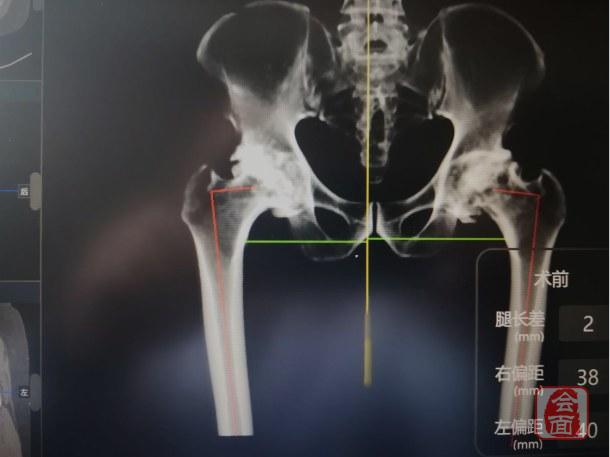

(AI HIP系统术前对患者臼杯大小、外展角、前倾角智能测量与评估)

为了精准的解决这个问题,魏瑄教授团队将张某的最新CT数据输入人工智能全髋关节置换规划软件“AI HIP”,自动识别股骨和骨盆,并建立了计算机数字三维模型,测量其骨缺损情况、恢复腿长、恢复股骨偏心距等数据。为确保手术万无一失,魏瑄除了准备好以上型号假体,还备用了与以上型号规格上下相邻的一大一小假体,保障手术顺利进行。在智能规划软件“AI HIP”的指导下,魏瑄主任医师、王金良副主任医师于2019年11月5日共同为张某进行了手术,从切开到缝合仅用54分钟即完成了“右侧全髋关节置换术”,术中置换仅用32分钟。术中发现假体的大小、位置、角度均非常理想。

术后返回病房的影像学结果显示,假体的大小、位置、角度和肢体长度与患者完全匹配,与术前计划完全一致。术日当天晚上,患者即可下地活动,睡眠和饮食均未受影响。